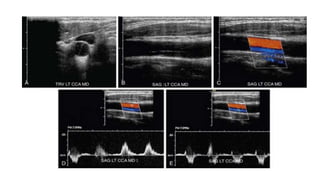

• Longitudinal gray-scale and color or power Doppler images of the

proximal and distal CCA, bifurcation, bulb extending into the ICA, and bulb

extending into the ECA.

• Transverse gray-scale and color or power Doppler images of the proximal

and distal CCA, bulb, bifurcation, proximal ICA, and proximal ECA.

• Spectral Doppler tracings from the proximal CCA, distal CCA, proximal ICA,

mid ICA, distal ICA, proximal ECA, and mid vertebral artery.

• PSV is recorded for each segment, and end-diastolic velocity (EDV) is noted if it

is more than 100 cm/sec.

• The PSVR is calculated by dividing the highest PSV in the proximal ICA or area

of stenosis by the PSV in the distal CCA.

• PSV in the distal CCA should always be measured 2 to 3 cm proximal to the

level of the carotid bulb.

• Several measurements, optimally three, of PSV should be obtained and the

highest velocity recorded.

Protocol • Longitudinal gray-scaleand color or power Doppler images of the proximal and distal CCA, bifurcation, bulb extending into the ICA, and bulb extending into the ECA. • Transverse gray-scale and color or power Doppler images of the proximal and distal CCA, bulb, bifurcation, proximal ICA, and proximal ECA. • Spectral Doppler tracings from the proximal CCA, distal CCA, proximal ICA, mid ICA, distal ICA, proximal ECA, and mid vertebral artery.

• PSV isrecorded for each segment, and end-diastolic velocity (EDV) is noted if it is more than 100 cm/sec. • The PSVR is calculated by dividing the highest PSV in the proximal ICA or area of stenosis by the PSV in the distal CCA. • PSV in the distal CCA should always be measured 2 to 3 cm proximal to the level of the carotid bulb. • Several measurements, optimally three, of PSV should be obtained and the highest velocity recorded.